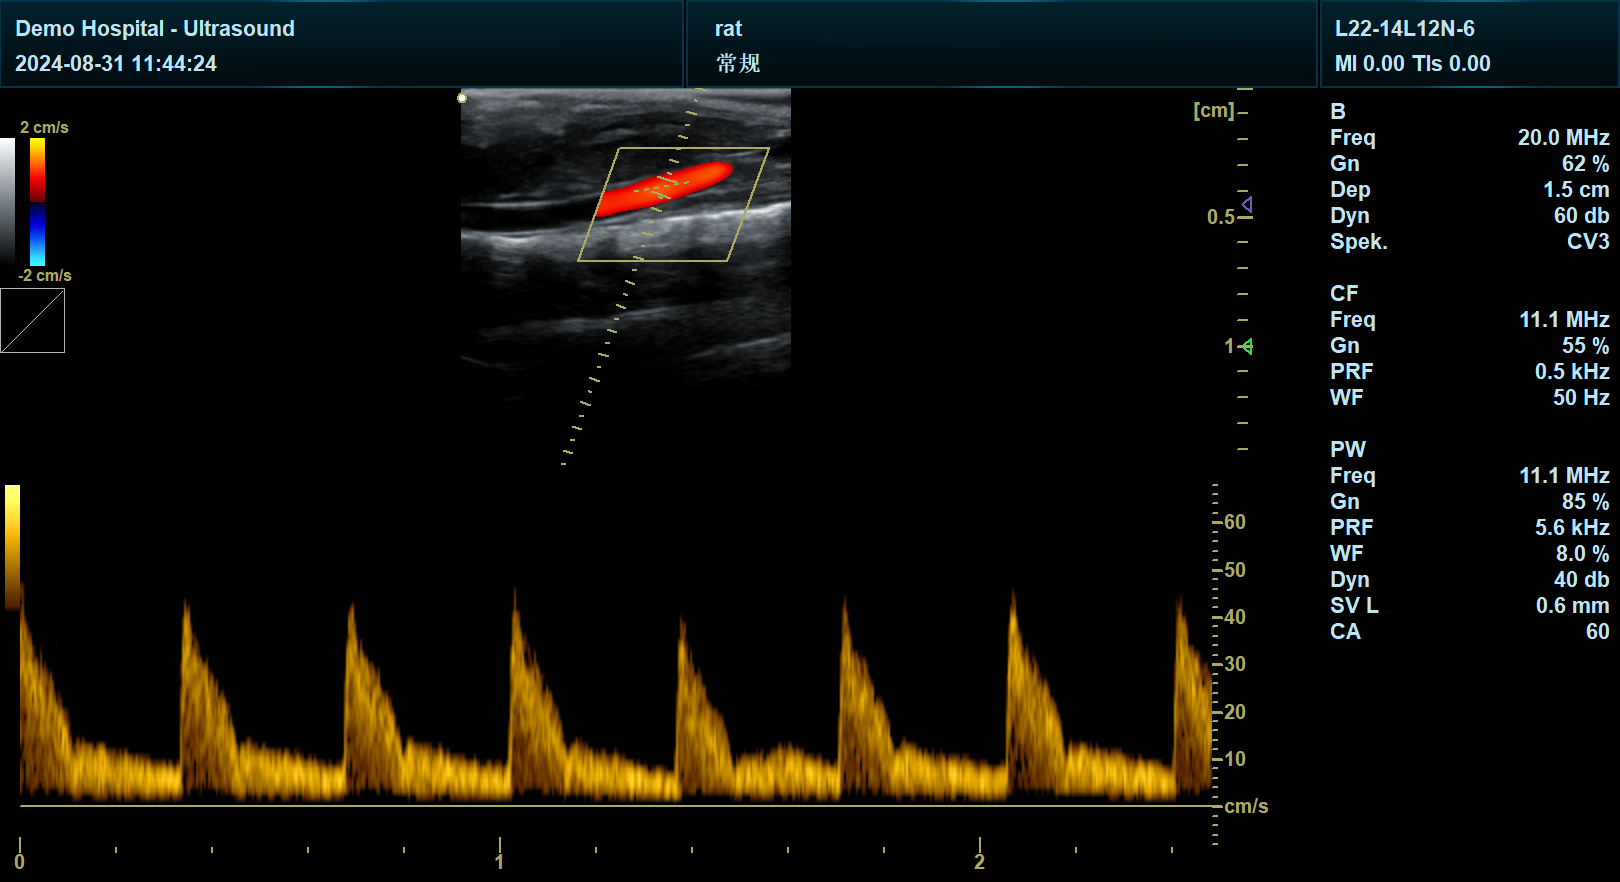

宜慧康YHK-DY30系列小动物超声采用18MHz超高频电子线阵探头,支持12-25MHz宽频带扫描,可清晰呈现小鼠心脏瓣膜、冠状动脉等微米级结构。其微型化探头设计(直径仅8mm)可深入小鼠胸腔,无需开胸即可获取高帧率(>100帧/秒)动态图像,彻底避免手术创伤对实验结果的干扰。

针对小动物组织声阻抗差异大的挑战,宜慧康研发自适应波束合成技术,通过动态调整超声波发射角度与接收灵敏度,将图像信噪比提升50%。在肿瘤模型研究中,该技术可清晰区分1.5mm以下的微小转移灶与周围正常组织,结合超声造影模式,甚至能捕捉肿瘤新生血管的“萌芽”阶段——当造影剂微泡在新生血管中聚集时,系统可量化血流灌注速度与密度,为抗血管生成药物研发提供关键证据。